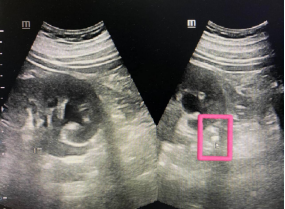

▲肾结石超声示意图

1. 结石本身

结石在超声上会显示为明显的强回声点,可初步判断大小、数量及位置,为后续治疗提供重要依据。